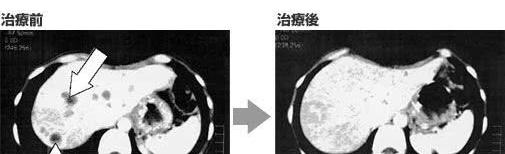

王先生,77岁,2014年4月确诊为左肺腺癌Ⅳ期,5月开始实施化疗共计6次,2016年复查,肺部病灶较前进展,再次化疗一周期后拒绝再次化疗,转为NK细胞免疫治疗。

2016年9月至2019年12月行NK细胞免疫治疗共计6次。

治疗获益:2017年胸部CT显示肿块大小为42*27*30(mm)、40*24*36(mm),2018年复查,病灶略缩小,大小为30*31*27(mm)、35*25*29(mm)。患者临床症状较前得到极大改善,精神、饮食、体重均恢复至病前水平,病情平稳